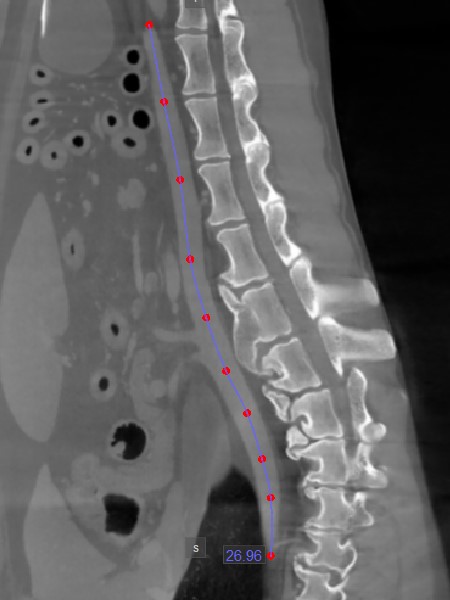

Distance

Use the Distance measurement tool to precisely measure the distance between two points with precision.

Select the Distance tool and assign it to one of the available mouse buttons. To calculate the distance, place two points on the active image slice by pressing on the appropriate position with the mouse. The distance between the two points will be automatically calculated. This tool is assigned to the middle mouse scroll button by default.

Modify the start and end point by using the Default tool from the left toolbar. The distance between the points will be automatically recalculated.